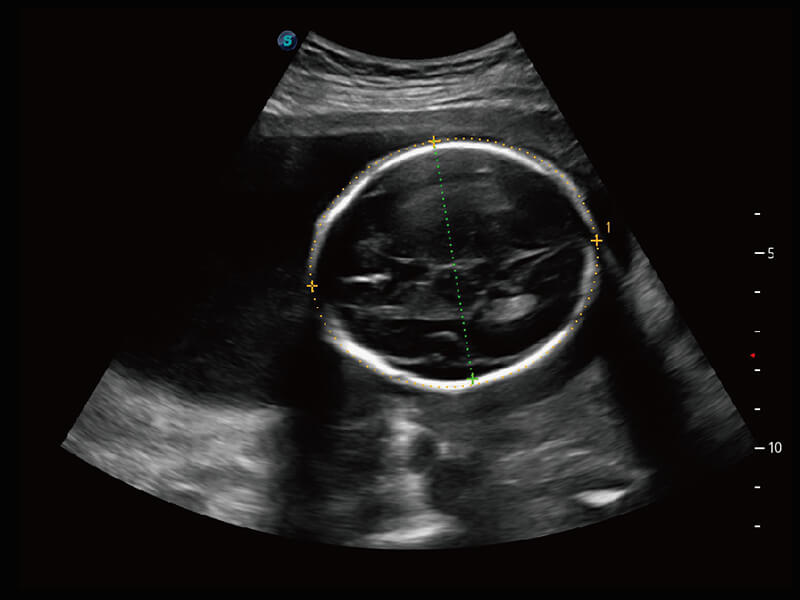

成像功能

性能优异的硬件架构,极大提升超声系统的运行效率和数据处理能力。相比以往超声成像系统,Wis+平台为您带来极快的响应速度和成像帧频,提升检查流畅度。

S60探头工艺,从前端信号处理每一个环节采集无损声学数据,真实还原组织原貌,再现解剖细节。